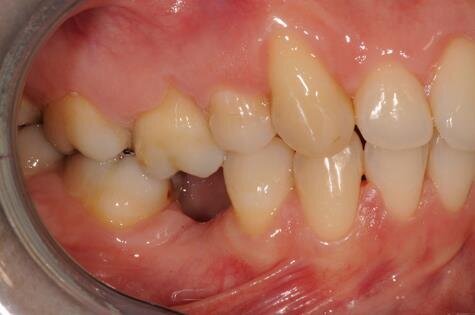

Figg. 2a-2c - Foto intraorali pretrattamento: visioni frontale (a), laterali (b).

All’esame clinico del viso si osservava una sostanziale simmetria bilaterale e corrette proporzioni facciali verticali frontali e laterali (Figg. 1a-1c). Il sorriso presentava un’adeguata esposizione degli incisivi superiori e dei corridoi buccali e la centratura della linea mediana superiore rispetto al volto. All’ispezione del cavo orale, invece, si riscontrava una lieve deviazione della linea mediana inferiore verso destra di circa 1 mm, con contestuale II Classe canina a destra (Figg. 2a-2c). La mancanza del primo molare inferiore di destra aveva prodotto lo spostamento mesiale, la mesio-inclinazione del secondo e terzo molare inferiore e l’estrusione del primo molare superiore. A sinistra, invece, era riscontrabile una I Classe canina e molare. Erano presenti un moderato affollamento nell’arcata superiore ed un lieve disallineamento degli incisivi inferiori. L’overjet era lievemente aumentato e l’arcata superiore appariva lievemente contratta, soprattutto a destra. Erano presenti recessioni gengivali multiple.